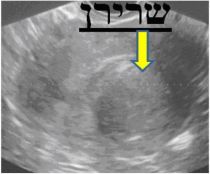

בדיקת האולטרה-סאונד היא בדיקה זמינה ופשוטה. הבדיקה מאפשרת לקבל פרטים על מבנה וגודל הרחם, מיקום וגודל השרירנים, רירית הרחם, אספקת הדם, מראה השחלות ועוד. כאשר מודגמים שרירנים על מסך הסריקה, מקובל לתעד זאת ולמדוד את גודלם. התמונות מודפסות ישירות ממסך המכשיר. ניתן לראות בהן צללים המייצגים שרירנים, וסמני מחשב המגדירים את מידותיהם.

| תרשים מספר 2: תמונות מבדיקות אולטרה-סאונד המדגימות שרירני רחם | ||